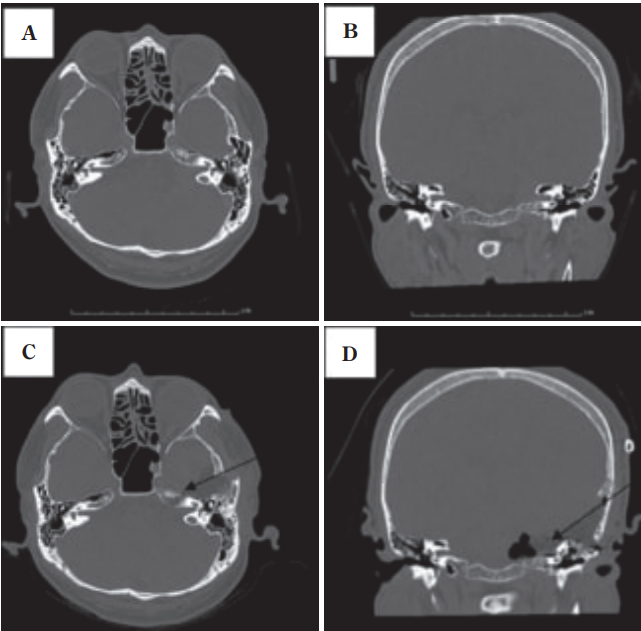

A&B:术前轴向和冠状面计算机断层扫描图像,显示岩骨水平的内听道。一个巨大的高颈静脉球延伸到后颅窝;C&D:术后图像显示切除的内耳道前壁和上壁。